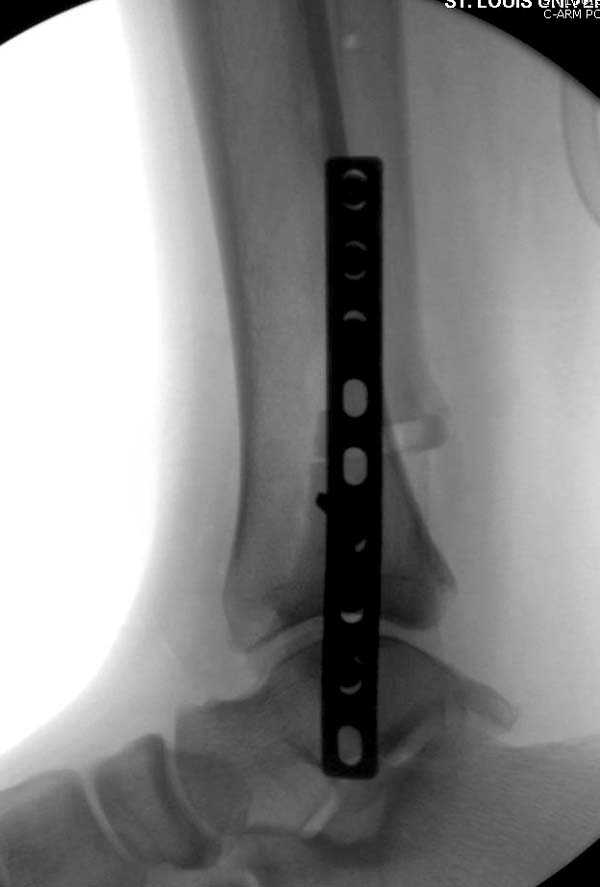

Здесь представлено решение похожей проблемы. Больной в течение года лечился консервативными мерами, и боли в голеностопе были основным показанием к операции.

Проведена обычная стандартная процедура по исправлению неудовлетворительного состояния голеностопного сустава, где кроме удлинения малоберцовой с применением compression tension device за проксимальный конец пластины, проведено замещение трикортикальным графтом из крыла, освобождение синдесмоза и медиальной щели от

фибротических масс с фиксацией.